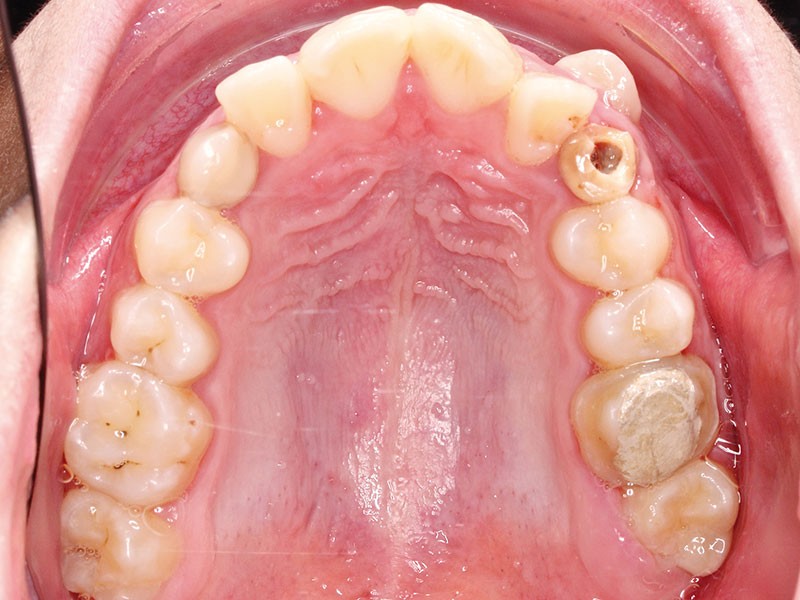

• Endo-buccal : Younesse présente un contrôle de plaque dentaire insuffisant, la persistance de 53 et 63, des soins en cours de réalisation sur 26 et 36, un encombrement maxillo-mandibulaire avec infravestibulotopie de 23 et une suspicion d’inclusion de 13 sur un schéma de Classe II subdivision droite (fig. 3 à 7).

L’examen parodontal révèle une gingivite généralisée ainsi qu’un parodonte très fin et une absence de profondeur vestibulaire.